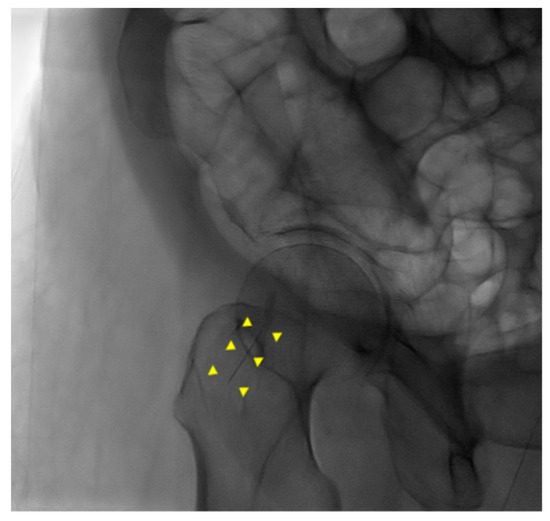

An 87-year-old female patient came to the emergency department with increased bilateral pleural effusion with pneumonia, and she was admitted for treatment. She had been bedridden with comorbidities, including old cerebral infarction, hypertension, and had left femur neck fracture with endoprosthesis for 4 weeks before admission. Her body mass index was 26.67 kg/m2. She was generally edematous. We drained pleural effusion, diagnosed as parapneumonic effusion, and administered intravenous antibiotics for the treatment of pneumonia with parapneumonic effusion. During hospitalization, her conditions were wax and wane, with aspiration pneumonia. On day 37 of hospitalization, her blood pressure was consistently low despite the use of a vasopressor. For arterial blood gas analysis (ABGA) to monitor the patient’s state of acidosis, we repeatedly performed puncture of the right femoral artery instead of the radial or dorsal artery. We used a 25 gauge and 16 mm length needle for femoral arterial puncture. After blood extraction, while drawing the syringe out of a femoral artery, the needle was disconnected from the syringe. The needle remained in the groin of the patient, and its location was not identified through portable ultrasonography. Radiography of the pelvic bone showed the needle fragment in the right groin (Figure 1). Fluoroscopic radiography revealed the exact location of the needle fragment (Figure 2). A surgical incision was performed to obtain the embedded needle in the soft tissue of the groin, without penetrating the femoral artery. The needle fragment was removed (Figure 3) completely without complications. The needle was bent as it was pulled out with mosquito forceps (Figure 3).

Figure 2. Fluoroscopic radiography of pelvic bone. A needle fragment showed in the right groin (yellow triangles).